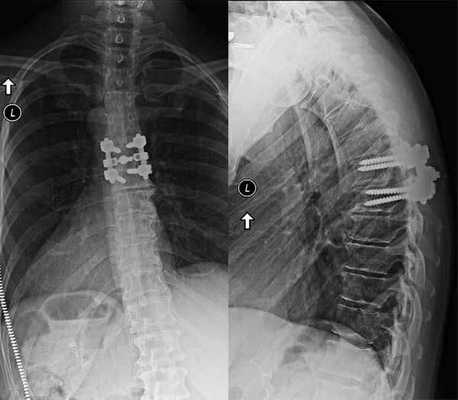

Рентгенография в передне-задней проекции:

установлен трубчатый ретрактор для левосторонней задней шейной микродекомпрессии межпозвонкового отверстия на уровне С6-С7;

в связи с развитием ложного сустава размещена конструкция,

фиксирующая латеральные массы: виден остаточный стеноз межпозвонкового отверстия после предыдущей операции на уровнях С5-С6 и С6-С7. Границы удаления ткани (красная пунктирная линия) при задней шейной микродекомпрессии межпозвонкового отверстия.